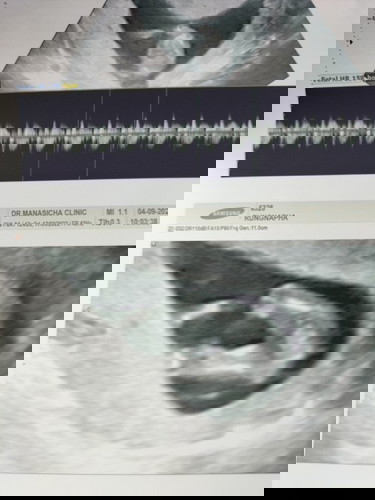

สอบถามหน่อยคะ ซาวด์ตอน12w6d คุณหมอบอก น่าจะผู้หญิง แต่ยังไม่ฟันธง รอน้องโตอีกนิด มีโอกาสเป็น ช. มัย

เท่าทีดูจากรูป น่าจะ ญ นะค่ะ